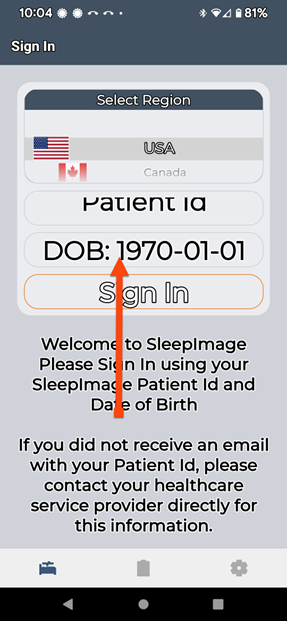

SLEEPIMAGE APP (Android)

SLEEPIMAGE APP (Android)

SLEEPIMAGE APP (Android)

SLEEPIMAGE APP (Android)

SLEEPIMAGE APP (Android)

SLEEPIMAGE APP (Android)

SLEEPIMAGE APP (Android)

SLEEPIMAGE APP (Android)

SLEEPIMAGE APP (Android)

SLEEPIMAGE APP (Android)

SLEEPIMAGE APP (Android)

SLEEPIMAGE APP (Android)

SLEEPIMAGE APP (Android)

SLEEPIMAGE APP (Android)

SLEEPIMAGE APP (Android)

SLEEPIMAGE APP (Android)

SLEEPIMAGE APP (Android)

SLEEPIMAGE APP (Android)

SLEEPIMAGE APP (Android)

SLEEPIMAGE APP (Android)

SLEEPIMAGE APP (iPhone)

SLEEPIMAGE APP (Android)

SLEEPIMAGE APP (Android)

SLEEPIMAGE APP (Android)

SLEEPIMAGE APP (Android)

SLEEPIMAGE APP (Android)

SLEEPIMAGE APP (Android)

SLEEPIMAGE APP (Android)

SLEEPIMAGE APP (Android)